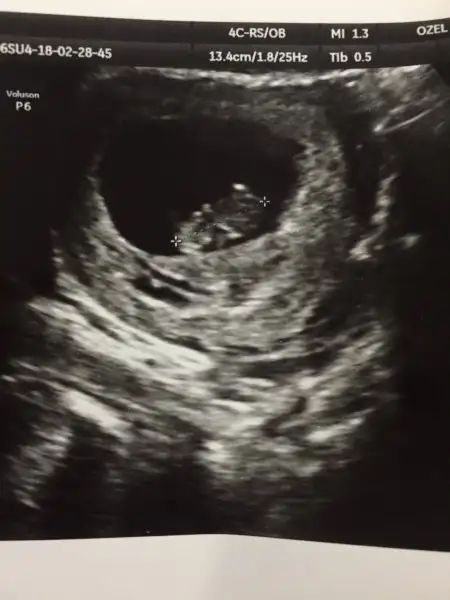

Teoriye göre benim de solda o zaman erkek :)